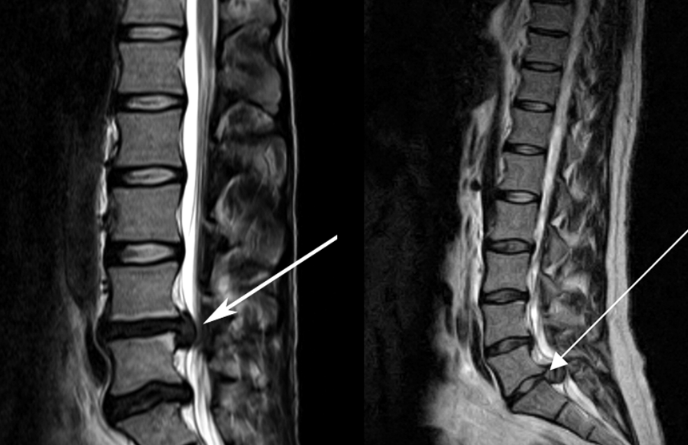

3、核磁共振(MRI):核磁共振沒有輻射,可以多方位成像(橫斷面、冠狀面、矢狀面和斜面),對解剖細節(jié)顯示較好,對組織結構的細微病理變化更敏感(如骨髓的浸潤),可以排除神經和脊柱腫瘤等。對于一些落到椎管的髓核組織也不會遺漏。